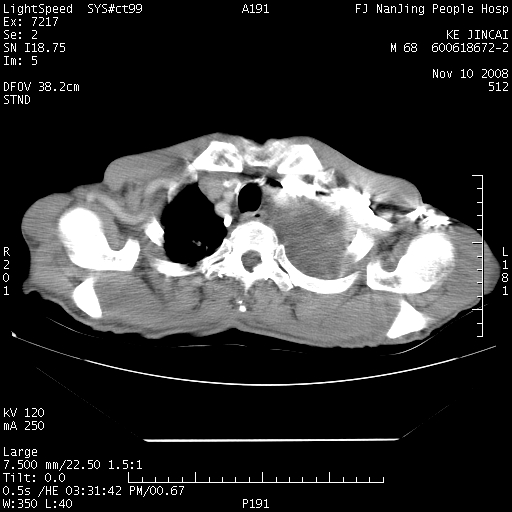

是个很有看头的病例,咋人气那么不旺?没多少人兴趣呢?这个病例几大怪:1   恶性肿瘤侵犯心肌左房怪,心肌一般不会被恶性肿瘤侵犯吧?2   左下肺均匀实变怪,内无含气,有别一般不张实变,含气肺泡完全为液体取代,而非一般不张实变的肺萎陷,冷不丁还以为是肿大的脾脏3   肿瘤本身怪,像tb肺不张4   这么有看头的病例没人气怪。呵呵。

追查病史,咳嗽,患者无发热,血象不高。据说2年前胸片检查怀疑肺ca曾行纤支镜检查,病理未见到癌细胞。无确切资料。

左肺恶性肿瘤侵犯肺动脉,左心房内瘤栓,胸膜转移。